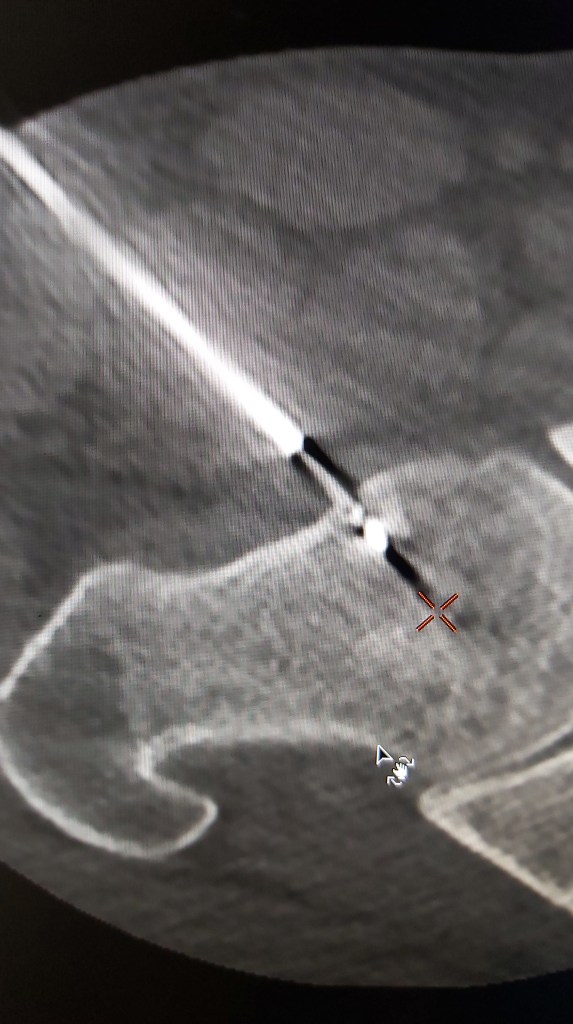

Kemik biyopsileri koaksiyel yöntemler ve tomografi kullanımı nedeniyle günümüzde artık yüksek doğrulukta lokal anestezi ile ağrısız olarak günübirlik olarak gerçekleştirilebilmektedir.